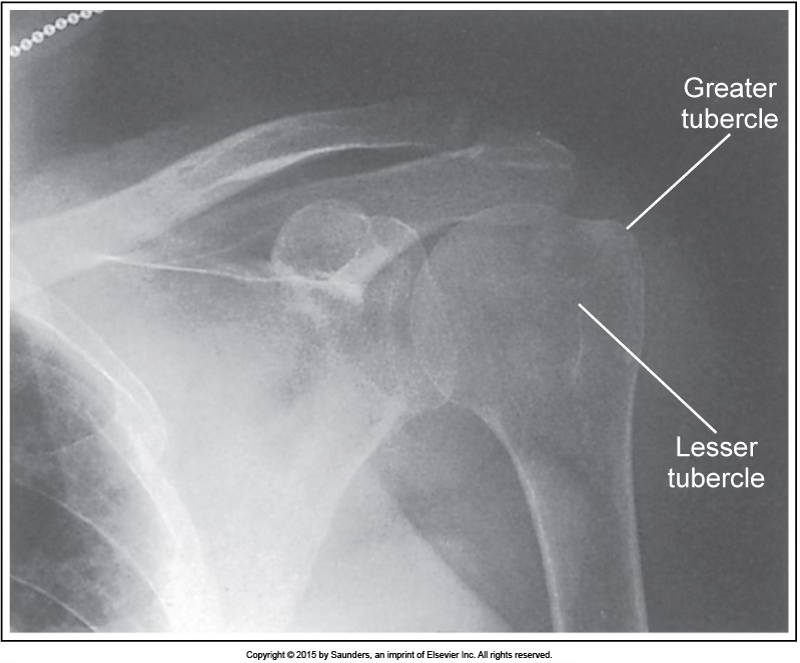

AP external shoulder

accurate positioning